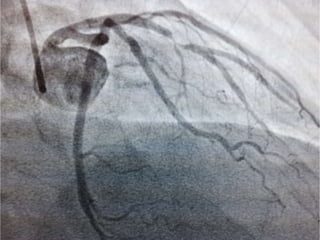

CASO CLINICO # 3

MASCULINO 65 AÑOS DE EDAD

DIABETES TIPO 2 DESDE HACE 15 AÑOS POBRE CONTROL METABOLICO

DISLIPIDEMIA. OBESIDAD GRADO II.

CUADRO CLINICO: ANGINA DE PECHO ATIPICA. CHEQUEO DE RUTINA. ECG DE

REPOSO NORMAL. PRUEBA DE ESFUERZO POSITIVA Y PRECOZ PARA ISQUEMIA.

TA 120/ 68 mm Hg. FC 67/min Fr 13/ min

Glucosa en Ayunas 215 mg /dL. Colesterol total 260 mg/dL, LDL 135 mg d/L

Creatinina 1.2 mg/dL

EXAMEN FISICO ANODINO

CASO CLINICO #3 MASCULINO 65 AÑOS DE EDAD DIABETES TIPO 2 DESDE HACE 15 AÑOS POBRE CONTROL METABOLICO DISLIPIDEMIA. OBESIDAD GRADO II. CUADRO CLINICO: ANGINA DE PECHO ATIPICA. CHEQUEO DE RUTINA. ECG DE REPOSO NORMAL. PRUEBA DE ESFUERZO POSITIVA Y PRECOZ PARA ISQUEMIA. TA 120/ 68 mm Hg. FC 67/min Fr 13/ min Glucosa en Ayunas 215 mg /dL. Colesterol total 260 mg/dL, LDL 135 mg d/L Creatinina 1.2 mg/dL EXAMEN FISICO ANODINO